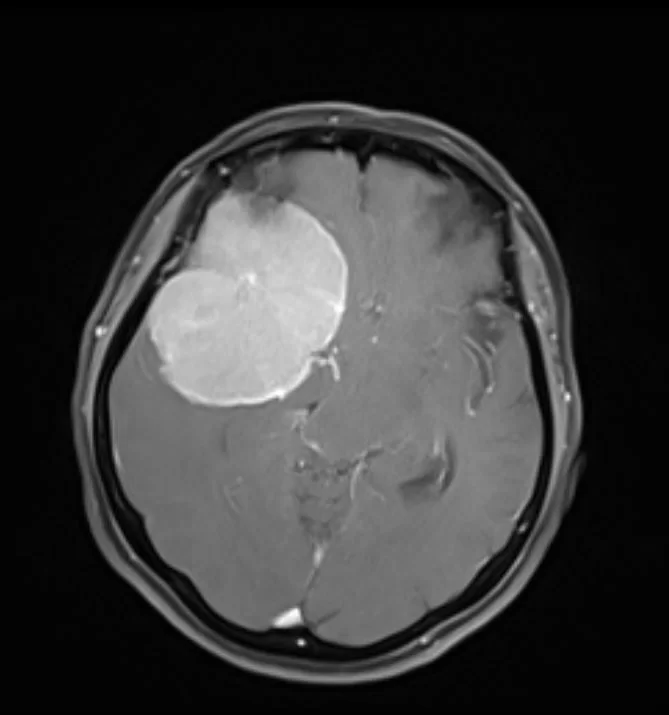

Ο απεικονιστικός έλεγχος με μαγνητική τομογραφία ανέδειξε ευμεγέθη εξεργασία δεξιά, συμβατή με μηνιγγίωμα πτέρυγας σφηνοειδούς οστού.

Διενεργήθη δεξιά πτεριονική προσπέλαση και εξαίρεση της βλάβης.